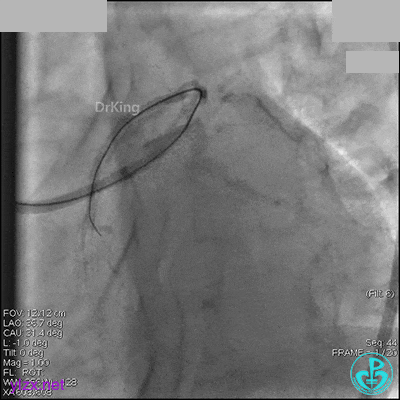

冠脉造影

入院次日冠脉造影显示粗大左主干末端中度狭窄,前降支开口严重狭窄,回旋支与前降支角度大,弥漫性长病变,严重狭窄,粗大右冠脉近中段弥漫性中重度狭窄。由于病变复杂,造影结束后先下台,择期再行介入治疗。